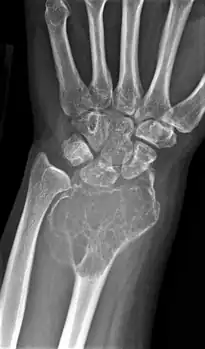

On X-ray, giant-cell tumors (GCTs) are lytic/lucent lesions that have an epiphyseal location and grow to the articular surface of the involved bone.[11] Radiologically the tumors may show characteristic 'soap bubble' appearance.[12] They are distinguishable from other bony tumors in that GCTs usually have a nonsclerotic and sharply defined border. About 5% of giant-cell tumors metastasize, usually to a lung, which may be benign metastasis,[13] when the diagnosis of giant-cell tumor is suspected, a chest X-ray or computed tomography may be needed. MRI can be used to assess intramedullary and soft tissue extension.

Front view X-ray one-year later it has grown